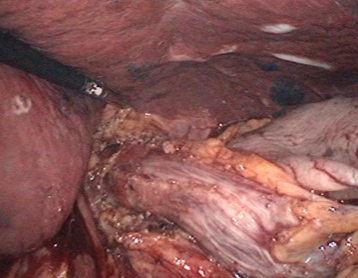

胃の周りにある血管に付着する脂肪を取りながら胃に入る血管を切り離して行きます。こうするとこでがん細胞のいる可能性のあるリンパを取り除くことができます。これを郭清と言い、がんの手術には非常に重要な操作です。

肝臓に行く血管の途中から、胃に向かう血管が(右胃動脈といいます)出てきます。

これも肝臓に向かう血管との分かれ道の部分で切り離します。

右胃があれば左胃動脈もあります。この血管は胃に入り込む最大の血管です。この血管の周りにも脂肪に包まれたリンパ節がありますから、しっかりと根元で切り離します。

右胃から左胃動脈に至まで、肝臓に向かう太い動脈(総肝動脈)に沿って血管の周りの脂肪が取り除かれています。

さらには脾臓に向かう血管の途中まで脂肪を取り除き、がん細胞が残ることがないように手術を行います。 - 6